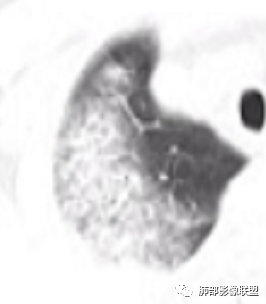

若晗: 结节十树芽十树雾

青藤之凉: 支原体肺炎的影像特征相对比较明显。有支气管壁增厚、支气管扩张样改变、支气管充气征。小叶小结节,有点状或者斑片状的浸润影、有实变影,表现为树芽征、树雾气征。

张延军: 树雾征,支原体感染

青藤之凉: 临床特点:①临床轻,影像重,病程较长。②儿童和青少年发病。

影像学特点:①支气管壁增厚、支气管周围炎。②腺泡结节、树芽征、树雾征(见病例1)。③结节融合,大片实变,部分边缘收缩。④分布上较广泛 。